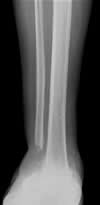

Nonunion: Ankle Case 2

Treatment in ProgressThese x-rays show treatment in progress after removal of bone and tissue at the nonunion site. Treatment consists of Ilizarov bone transport and compression to move a segment of bone downward to obtain fusion of the ankle joint. |